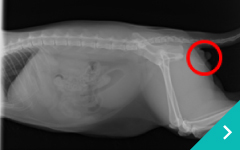

当院では院内に「腎臓病センター」を開設し、感染症や中毒による急性腎不全や高齢化に伴う慢性腎不全、ネコの尿管結石などの治療を行っています。

「血液透析」「結石破砕装置」「2.8mm細径内視鏡」 「SUBシステム」「尿管ステント」を組み合わせる事により、今までにない新たな治療に取り組んでいきます。

SUBシステム

SUB

システム

ステント治療

ステント

治療